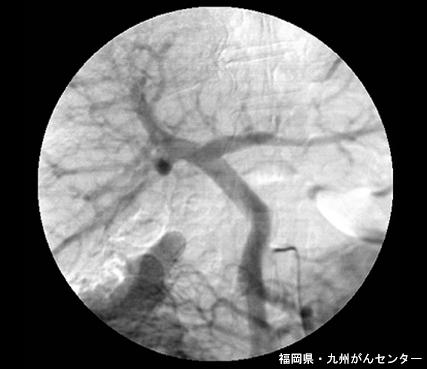

Tumor del Estroma Gastrointestinal (GIST) del Duodeno descubierto mediante un examen de anemia

Fukuoka Pref., Centro Kyushu de Curaciones de Cáncer

Tumor no Epitelial Maligno/Leiomiosarcoma

duodeno/ascendente

método de exámen

diámetro mayor del tumor